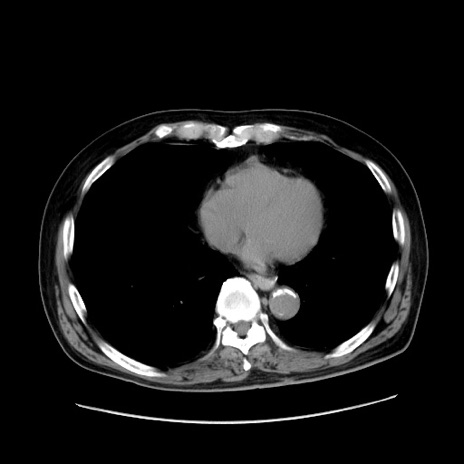

症例30(横断像)

【症例】80歳代男性

【主訴】臍周囲痛

【現病歴】約6時間前から臍下部痛が出現。次第に腹部膨隆・背部痛も生じてきたため来院。背部痛の場所は変化しない。

【身体所見】意識清明、BT 36.3℃、BP  131/87mmHg、P 87bpm、SpO2 100%(RA)、臍周囲自発痛・圧痛あり、反跳痛なし、自発痛部位に一致して板状硬あり、腹部膨隆、腸雑音減弱、CVA tenderness両側陰性。